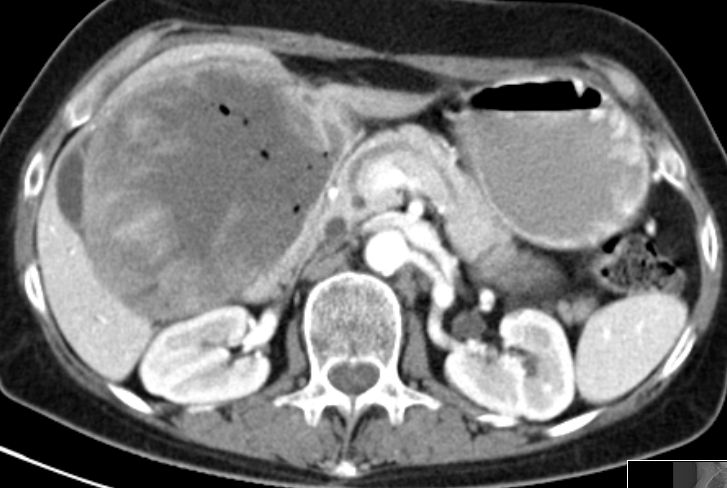

| Duodenum | Große Raumforderung im rechten Oberbauch einer53-jährigen Frau.

Histologisch alveoläres Rhabdomyosarkom, wahrscheinlich von der Duodenalwand ausgehend.

Lufteinschlüsse durch Verbindung zum Darm.![]() | |||||||||||||||||||